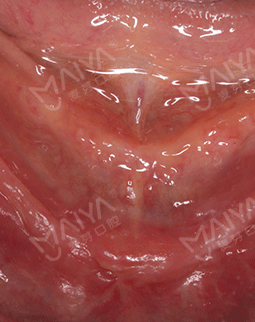

2016年11月 全口牙齿都缺失了,相信麦芽的医生!

缺牙的苦楚,我比谁都明白。年纪大了,就希望吃点好的,出去逛逛,享受下晚年的安逸和幸福。缺牙的年轻人啊,要吸取我的教训,别等一口好牙都稀稀拉拉的掉了,才考虑修复,期间的健康、生活的质量都直线下降,实在不值得。